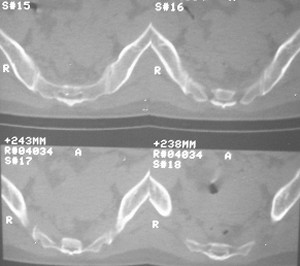

标题: CT7246: F,30岁,下腰痛,同事的片子,请老师们看看,初 [打印本页]

标题: CT7246: F,30岁,下腰痛,同事的片子,请老师们看看,初

典型的双侧骶髂关节致密性骨炎.

致密性骨炎,好发于骶髂关节的髂骨侧的耳状面(少见部位有骶骨,耻骨联合,甚至锁骨也有报道),好发于育龄期的妇女,多对称发病

何谓髂骨致密性骨炎?髂骨致密性骨炎是发生于髂骨耳状关节部分的骨质密度增高性疾病。病因迄今不明,可能与妊娠、机械性劳损、病灶性炎症有关。本病好发于20~35岁的育龄妇女,偶见男性。

髂骨致密性骨炎的临床表现与体征:腰骶部疼痛,多呈慢性、间歇性酸痛、隐痛,可向一侧或双侧臀部及大腿后侧扩散,但不沿坐骨神经方向放射,步行、站立、负重及劳累后加重,咳嗽、打喷嚏不能使疼痛明显加重,休息后症状减轻。患者腰骶角加大,局部有压痛和肌紧张,骨盆分离和挤压试验阳性,“4”字试验阳性,化验检查多在正常范围内。x线检查,骶髂关节间隙整齐清晰,靠近骶髂关节面中的髂骨耳状关节部分骨质密度增高,呈均匀浓白边缘清晰的骨质致密带,骨小梁消失,无骨质破坏。本病应注意与早期强直性脊柱炎、骶髂关节结核相鉴别。